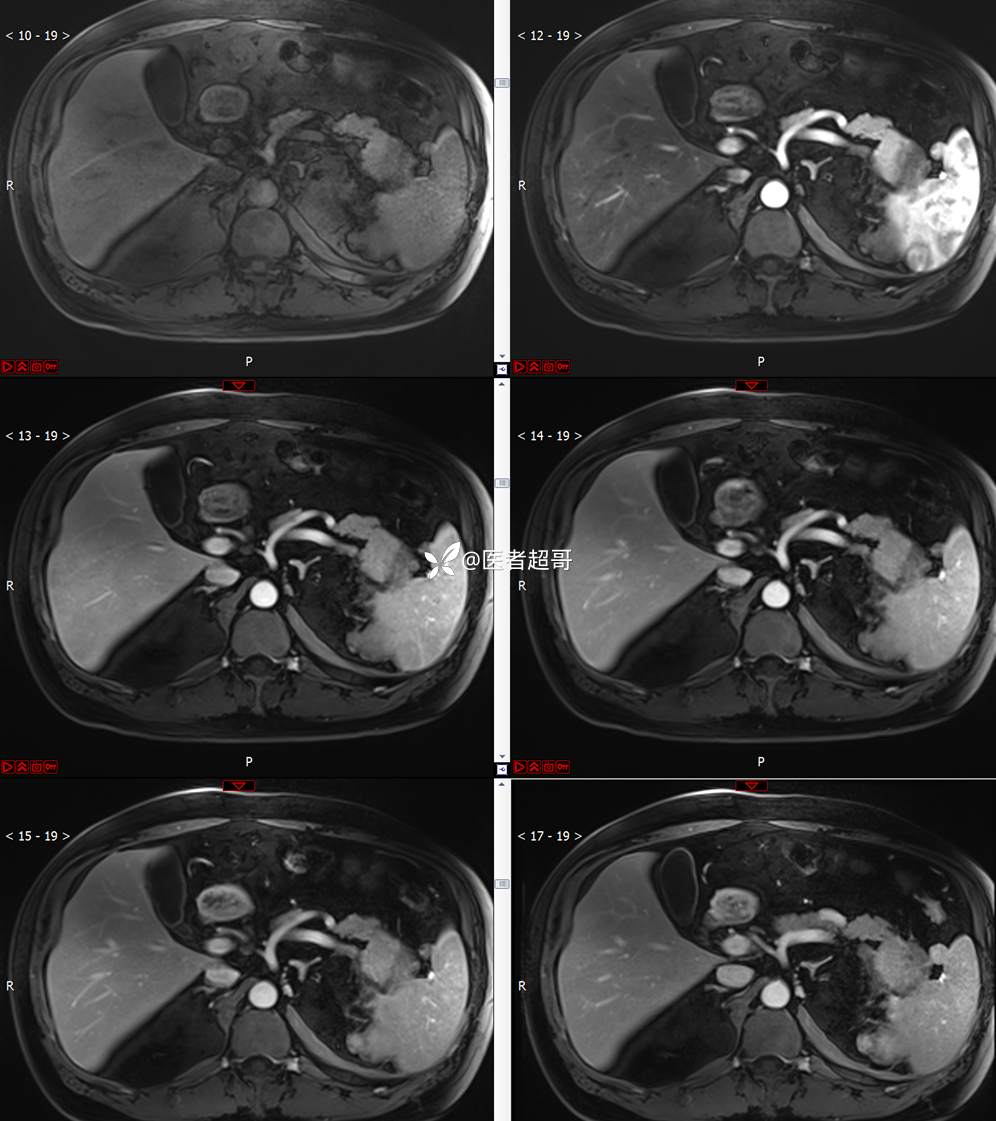

主 诉:查体发现左肾肿物9天。

现病史:患者9天前于附属医院行常规腹部CT检查时,发现左肾占位性病变并肾周脂间隙软组织增多,自述无明显腰腹部不适,无尿频、尿急、尿痛及肉眼血尿,未予特殊治疗,患者近期无头晕头迷,胸闷气急,腹胀腹泻及其他部位明显不适,遂至我院就诊,门诊以“肾肿物”收入院,患者自发病以来,精神可,睡眠饮食可,大便正常,体重无明显减轻。